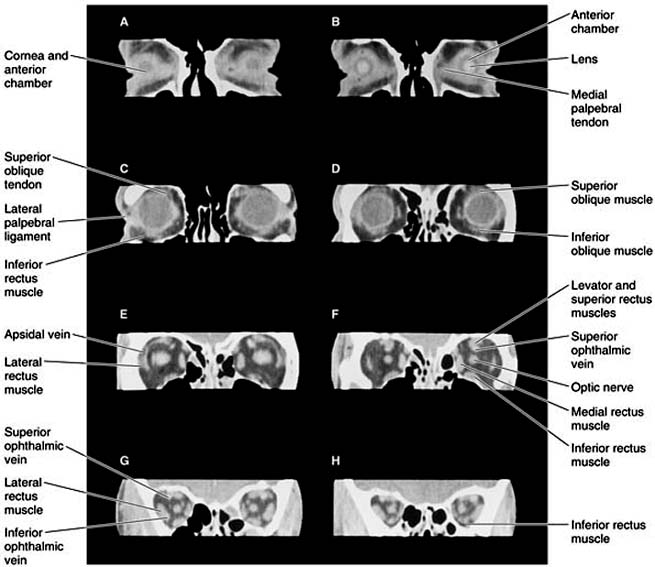

Figure 13-2

Figure 13-2: Coronal computer reconstructions from axial CT sections. A: Most anterior section. H: Most posterior section. Note detailed demonstration of ocular and orbital structures.